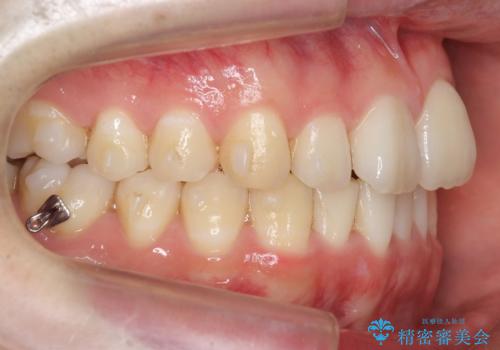

奥歯を後ろに移動させるために、矯正用のミニスクリューを用いました。(インプラント矯正)

- マウスピース矯正

- 1年10ヶ月